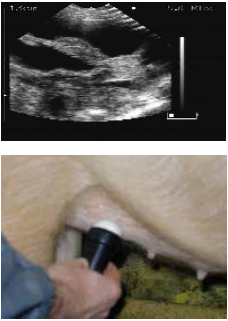

扫描仪的探头涂上耦合剂后置于腹股沟部。

The scanner head is applied gel and is placed in the groin.

缓慢地移动探头,直至出现胚胎清晰的图像。

lowly move the scanner head around until there is a clear picture of the fetus.

位置1的超声波图像.

Ultrasound image position 1.

位置2的超声波图像.

Ultrasound image position 2.